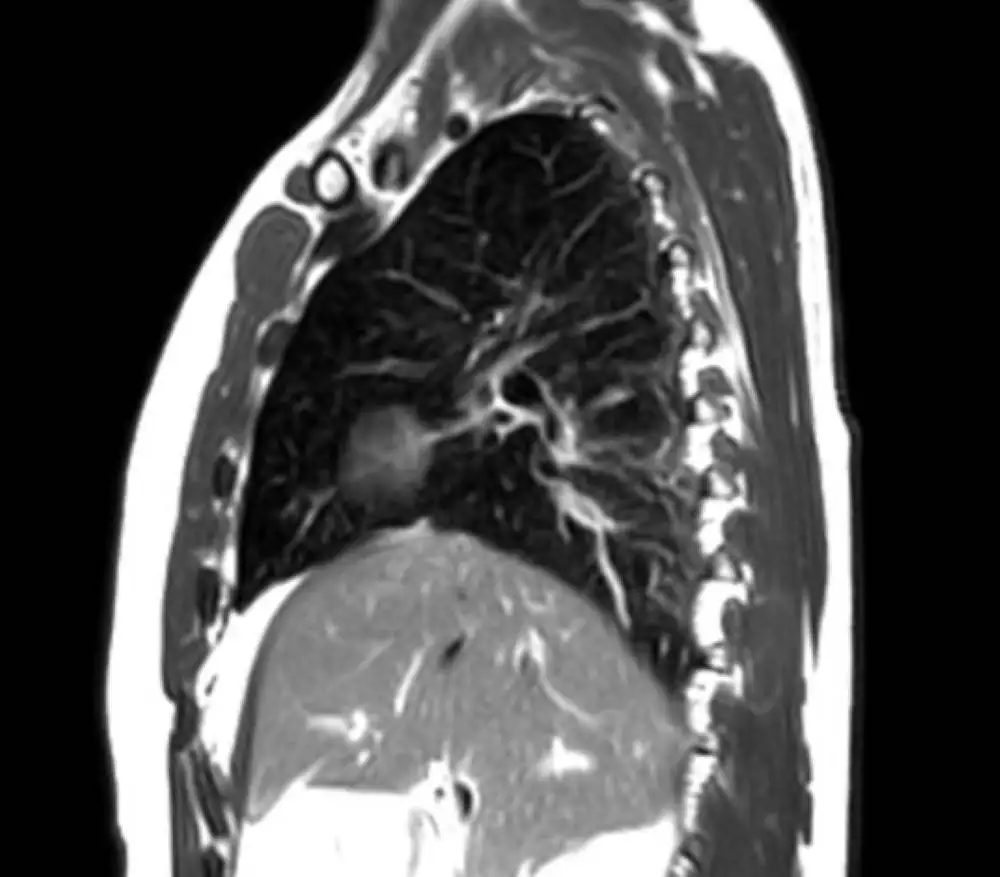

Eine Magnetresonanztomographie des Brustkorbs, kurz die MRT Thorax genannt, ist ein medizinisch bildgebendes Verfahren. Die MRT Thorax Untersuchung stellt mithilfe von Magnetfeldern und Radiowellen insbesondere die Lungenflügel, das Herz, die großen Blutgefäße und das Mediastinum detailliert dar. Vor allem bei Verdacht auf Tumore oder andere komplexe Erkrankungen im Brustbereich kann eine MRT Thorax aufschlussreich sein.

Bei der Thorax MRT-Untersuchung wird ein Hochfrequenzsystem verwendet, das die Ausrichtung dieser Atomkerne ändert. Während die Kerne in ihre ursprüngliche Position zurückkehren, senden sie Signale aus. Diese Signale werden von speziellen Detektoren aufgefangen und in Bilder umgewandelt. Das Ergebnis sind detaillierte Querschnittsbilder des Brustkorbs, die es ermöglichen, die inneren Strukturen wie Lungen, Herz, große Blutgefäße und das Mediastinum in hoher Auflösung darzustellen.

Die MRT Thorax erstellt viele Bilder von verschiedenen Schichten des Brustbereichs, die anschließend zu einem dreidimensionalen Bild zusammengesetzt werden.